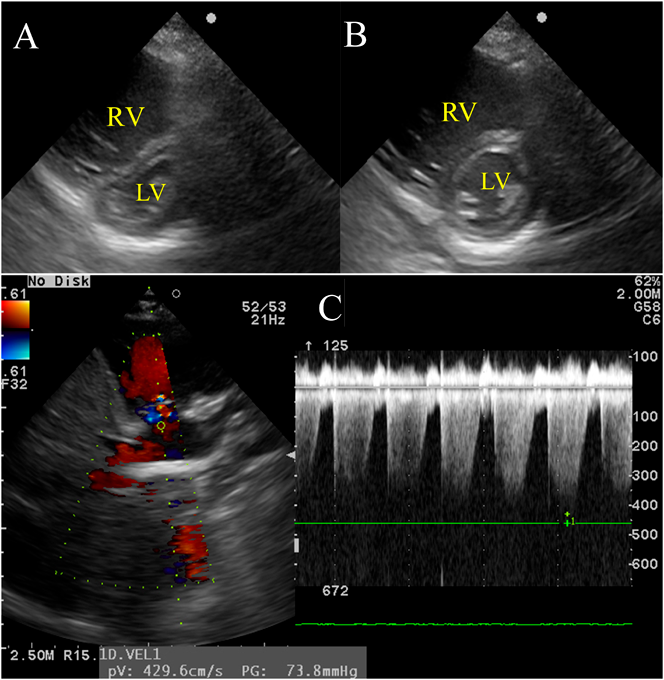

Chest radiography showed no abnormalities in the lung field and no cardiac enlargement. The main pulmonary artery was slightly enlarged (Fig. 1). Electrocardiography (ECG) showed a sinus rhythm with right axis deviation (Fig. 2). Echocardiography revealed enlargement of the right ventricle (RV) and right atrium (RA) and bulging of the interventricular septum to the left ventricle (LV). Tricuspid regurgitation (TR) was moderate, with a peak TR jet velocity of 4.29 m/s (Fig. 3). RV pressure was estimated to be 73 mmHg plus RA pressure; accordingly, severe PAH was suspected. Contrast echocardiography was performed to differentiate diseases causing hypoxemia. Microbubbles were stagnant in the RA and RV, with RV function markedly deteriorated, and did not enter into the left heart. A sildenafil (1 mg/kg) administration test was carried out through a nasogastric tube under oxygen administration using a high flow nasal cannula. One hour later, echocardiography showed that the abnormal arrangement of the interventricular septum had become normally round, that TR had improved to mild, and that the peak TR jet velocity had attenuated to 2.89 m/s (Fig. 4). Tachycardia and tachypnea disappeared, and blood pressure came up. Based on his dietary history, thiamine (30 mg) was injected intravenously followed by oral thiamine (25 mg/day) continued for possible cardiovascular beriberi due to vitamin B1 deficiency. Since idiopathic PAH could not be ruled out entirely, tadalafil (1 mg/kg/day) was started from the day of admission. TR eventually disappeared on echocardiography on the same day. The RV and the RA gradually became smaller.

Fig. 3 (A) On admission, echocardiography (short axis view) at end-systole revealed the right ventricle enlarged and the interventricular septum deformed. (B) At end-diastole, the right ventricle remained enlarged. The septum was round. (C) A peak regurgitant velocity across the tricuspid valve was 4.29 m/s. Systolic right ventricular pressure was estimated to be 73 mmHg plus right atrial pressure